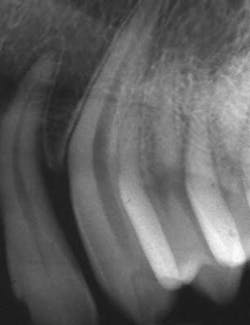

Last month we asked you to Diagnose the X-ray below and send in your answers on what you think the operator may have done wrong. Today we provide you with the image’s diagnosis!This month we did not receive a correct diagnosis to February’s X-ray image. Be sure to send in your diagnosis for this month’s Diagnose the X-Ray for a chance to win!

X-ray answerThere were several contributing factors that created the exposing and processing problems found in this image. The overall dark tone, or lower contrast to this image, is the result of the image being overexposed. There are also two abnormal lines found on this film that are the result of processing problems. The horizontal, narrow, slightly curved light density lines are scratches caused when the emulsion was pinched and ripped from the film base during processing. This is likely due to an automatic processor rack or roller being out of position. The angled vertical lines, considered roller marks, are caused when the film turned (skewed) slightly during processing. Turning of the film can also be the result of a rack or roller being out of position. The nature and directions of the artifact scratches and roller marks would prove that this type of processing problem is unique to the roller transport process.Tips and TricksIn order to avoid this problem, I recommend the following:

- In this situation, a rack may have been out of alignment or a damaged roller may need to be replaced. To correct the film scratches during processing, a very close examination of the racks and rollers are required.

- Image density and contrast quality can be improved by evaluating and adjusting the exposure technique.